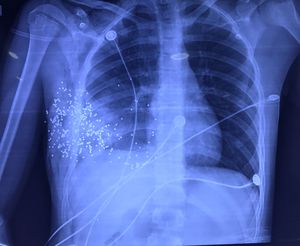

Xray of the chest

Accidental bullet shot penetrating the chest of a young 19 year old male patient. The patient had a CT Scan and urgent thoracotomy